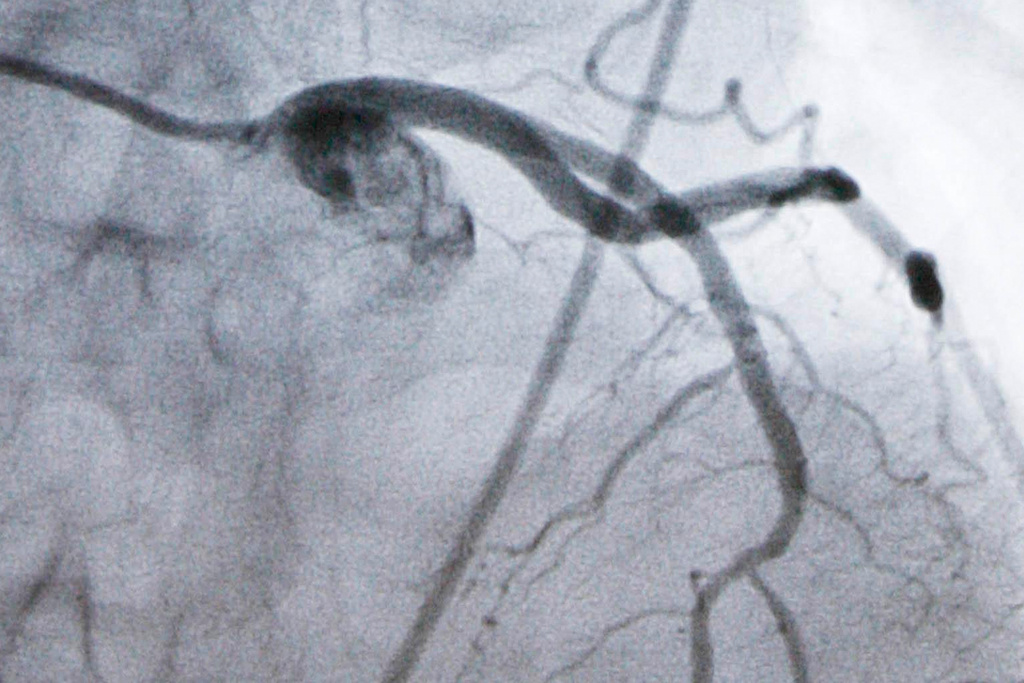

FILE - A monitor shows an artery during a catheterization lab heart procedure in Burlington, Vt., Tuesday, Sept. 23, 2008. (AP Photo/Toby Talbot, File)